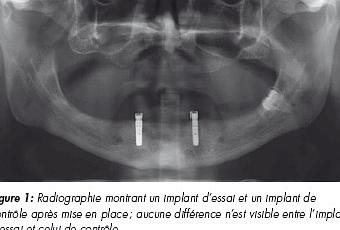

Le design de l’étude était un essai clinique multicentrique, de non-infériorité, en bouche divisée, en double aveugle, contrôlé, randomisé et prospectif conduit sur huit sites dans cinq pays (Allemagne, Italie, Belgique, Pays-Bas et Suisse) dans le but de montrer que les implants Roxolid® sont au moins aussi performants que ceux en titane. Des patients présentant une mandibule totalement édentée ont été recrutés selon les critères d’inclusion et d’exclusion définis.4 L’étude a été réalisée selon les règles des bonnes pratiques cliniques (conformément à la norme ISO 14155) et approuvée par les comités d’éthique de tous les sites d’étude. Tous les patients ont produit leur consentement éclairé. Selon le schéma de l’étude, chaque patient a reçu deux implants SLActive® Bone Level Ø 3,3 mm, soit un implant de contrôle (Ti) et un implant d’essai (Roxolid®) dans la région interforaminale (figure 1). Une prothèse amovible sur deux piliers LOCATOR ® a été placée. La mise en place du pilier et de la prothèse a été effectuée 8 à 10 semaines après l’intervention chirurgicale, avec des visites de suivi effectuées après 6 mois, 1 an (levée de l’aveugle) et 2 ans. À 1 et 2 ans, la survie de l’implant et le taux de réussite, la modification de l’os crestal péri-implantaire, le saignement au sondage (BoP, bleeding on probing), l’indice de plaque (PI, plaque index) et l’indice de saignement sulculaire (SBI, sulcus bleeding index) ont été évalués.